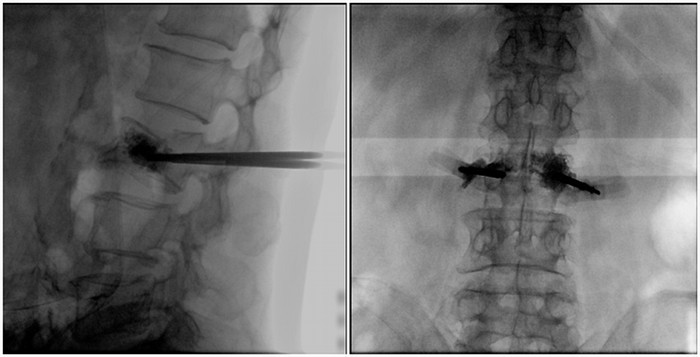

普愛醫療大平板一體式移動C臂采用30cm×30cm的平板探測器,能在手術過程中,為醫生提供更廣闊的視野范圍,帶給醫生更全面的影像信息。在進行脊柱類手術時,一次曝光即可呈現全節段腰椎,避免因為呈像不全而導致重復曝光,不僅提高了手術效率,而且避免醫生吸收過量的輻射。